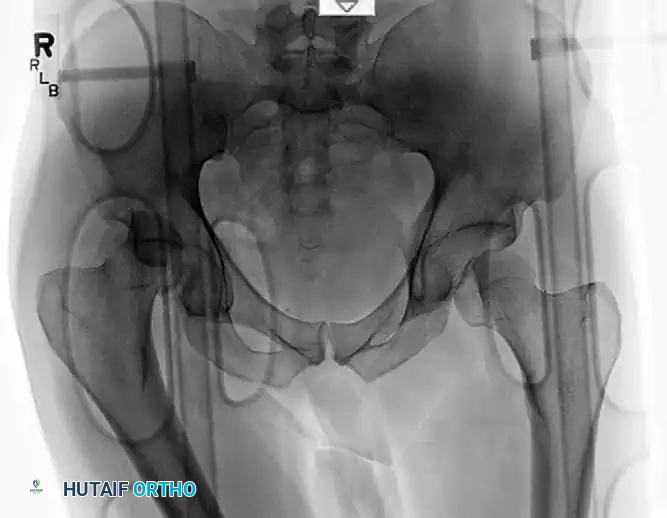

COMPLEX SCENARIOS: CONCOMITANT PROXIMAL FEMORAL FRACTURES

High-energy trauma resulting in posterior hip dislocation can occasionally cause concomitant fractures of the proximal femur, including femoral head fractures (Pipkin classifications) or subtrochanteric fractures.

When a subtrochanteric fracture occurs in conjunction with a hip dislocation, closed reduction of the hip is often impossible because the proximal femur cannot be manipulated via the distal shaft. These complex fracture-dislocations require open reduction and rigid internal fixation.

Fixation with a Proximal Femoral Locking Plate

For subtrochanteric fractures associated with complex hip trauma, a proximal femoral locking plate provides excellent biomechanical stability.